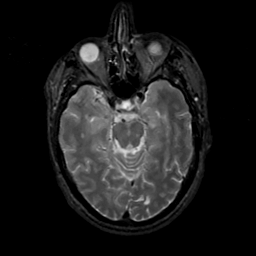

MR Study #17, July 7, 1991 -- Slice #18